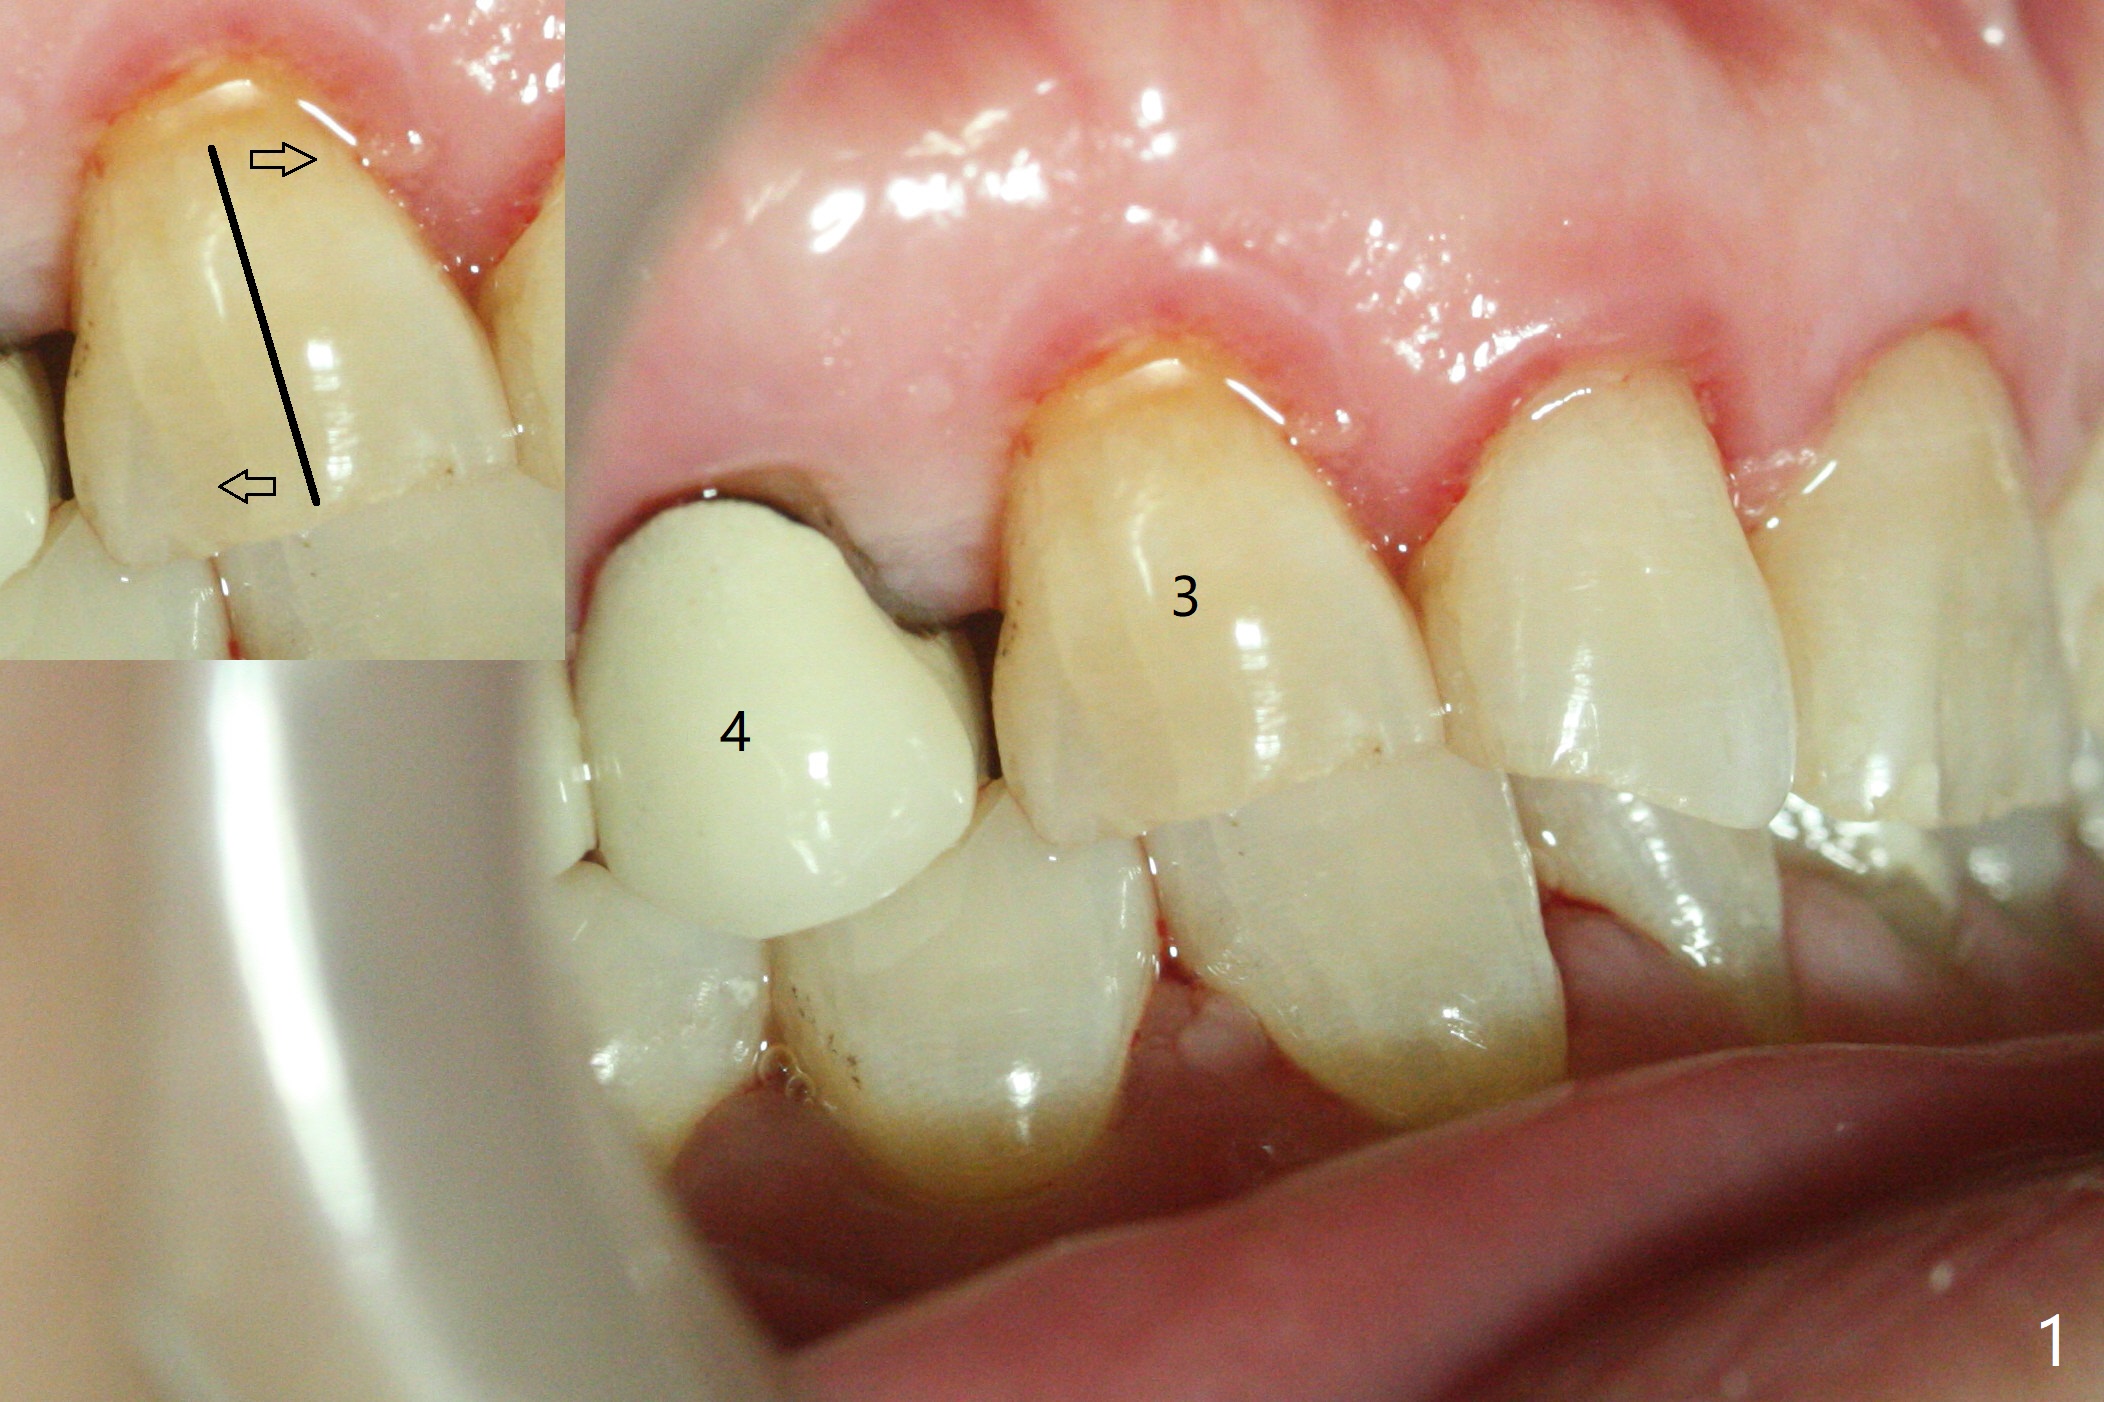

A 54-year-old man returns to office for UL7 upright 6 months post UR5 implant crown cementation (Fig.5,6). The ultimate purpose is to place implants at UL6 and LL 7. The latter will reduce severe occlusal wear especially in the lower anterior teeth (Fig.3,4). To solve the diastema between UR3 and 4 (Fig.1), the bracket at UR3 is placed in the height of contour (Fig.1 insert, Fig.4). Arch wire sequence may automatically close the diastema (Fig.1 insert arrows). In addition to tilting of UL7 (Fig.7), there are diastemata between U1s and UL3 and 4 (Fig.8,9 arrowheads). The patient is not tolerating orthodontic treatment well and requesting finishing the treatment early. We are considering mesializing UL7 instead of upright by placing a mini-implant between UL4 and 5 (Fig.10). There will be less interference of the roots of UL7 with the crown of the impacted UL8. There appears more space for a 1.6x8 mm mini-implant between UL4 and 5 (Fig.11) and UL 3 and 4 (Fig.12). Finally a mini implant is placed distal to UL7.